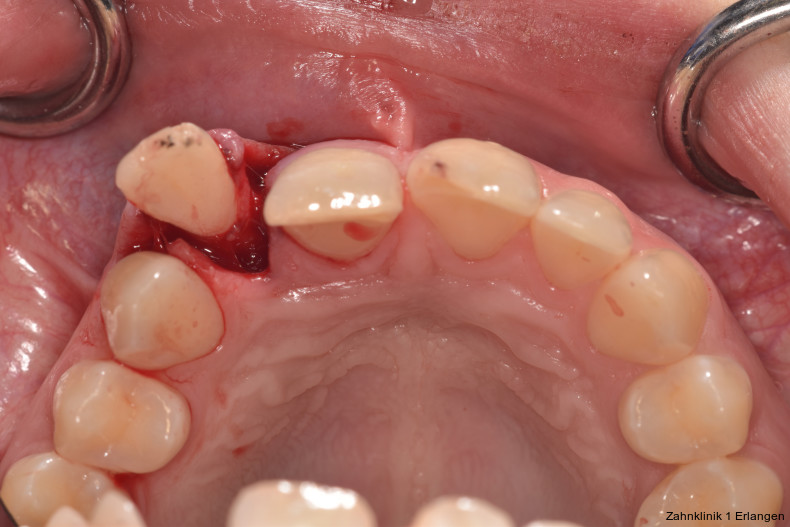

Bei Pulpaexposition ist die oberste Prämisse der Erhalt der Vitalität des Zahnes. Vor allem bei jungen Patienten und bei nicht abgeschlossenem Wurzelwachstum, aber auch bei erwachsenen Patienten ist die Vitalerhaltung die Methode der Wahl. Dabei spielen die Dauer und die Größe der Exposition keine wesentliche Rolle.10 Die oberste Gewebeschicht sollte zunächst im Sinne einer Mikropulpotomie angefrischt werden, was mit einem Diamantschleifer unter Wasserkühlung durchgeführt werden kann. Nach Blutstillung, zu der Natriumhypochlorit tropfenweise appliziert werden kann, wird das Sistieren der Blutung kontrolliert. Ist dies verifiziert, wird ein biokompatibles Material in direktem Kontakt mit dem Gewebe aufgebracht und der Zahn anschließend adhäsiv verschlossen.10 Dauert die Blutung an, beispielsweise weil der Unfall bereits mehr als 24 Stunden zurückliegt, kann tiefer pulpotomiert werden. Da eine traumatisch geschädigte Pulpa in der Regel vor dem Unfall gesund war, ist die Heilungskapazität meist sehr gut.11 Auch bei bestehender Exposition zur Mundhöhle hin über einen Zeitraum von Tagen kann die Pulpotomie noch hohe Erfolgsraten erzielen.

Tierexperimentelle Studien konnten zeigen, dass selbst bei über mehrere Tage hinweg freiliegender Pulpa Bakterien aus der Mundhöhle nicht tiefer als 2 mm in das Gewebe eindringen konnten.12 Kritisch ist dabei die erfolgreiche Blutstillung, die nach ca. fünf Minuten erreicht sein sollte. Die Erfolgsquoten der Pulpotomie nach Zahntrauma liegen deutlich über denen der direkten Überkappung bei über 90 Prozent. Dies ist auch in der revidierten Fassung der S2k-Leitlinie zum dentalen Trauma bleibender Zähne herausgestellt.3 Es ist zu beachten, dass bei begleitender Dislokationsverletzung die Durchblutung der Pulpa eingeschränkt oder sogar komplett unterbunden sein kann, was das Risiko des Misserfolges vitalerhaltender Maßnahmen signifikant erhöht.13 Daher sollte in solchen Fällen die Pulpektomie durchgeführt werden. Dies gilt ebenso bei umfangreichem Hartsubstanzverlust, wenn die definitive Restauration zusätzlich intrakanalär verankert werden muss.

Bei ausgeprägten Dislokationsverletzungen stellt die Schädigung des Parodonts die dominierende Verletzung dar, die auch zu Spätfolgen und Komplikationen führen kann. Verletzungen des Endodonts sind im Hinblick auf den Zahnerhalt vergleichsweise unbedeutender, da die Wurzelkanalbehandlung eine Infektion relativ sicher verhindern oder beseitigen kann. Die Erstversorgung schließt im Wesentlichen die Repositionierung und Schienung zur Ruhigstellung der betroffenen Zähne ein.3 Spätestens ab einer Positionsveränderung von 2 mm ist bei Zähnen mit abgeschlossenem Wurzelwachstum sicher von einem irreparablen Schaden der Pulpa auszugehen.2 Wichtig ist es, zeitnah, in der Regel während der Schienungsdauer, die Wurzelkanalbehandlung einzuleiten, um eine bakterielle Besiedelung des Wurzelkanals zu verhindern. Dabei reicht es zunächst aus, den Zahn zu eröffnen, desinfizierend zu spülen und eine medikamentöse Einlage einzubringen. Wird dies unterlassen, entwickeln sich bei entsprechender parodontaler Schädigung infektionsbedingte Resorptionen, die rasch fortschreiten und innerhalb relativ kurzer Zeit bis zum Zahnverlust führen können.